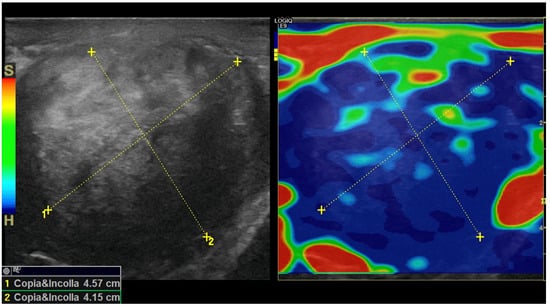

In addition, real-time strain elastography (SE) was carried out as an additional diagnostic tool for evaluating tissue elasticities when conducting US. Specifically, SE was performed by employing repeated compressions and decompressions with the transducer using a freehand technique. The pressure applied was adjusted according to the visual indicator for compression presented on a video screen. Tissue elasticity was calculated in real-time, and stiffness of tissues was displayed as a color-coded overlay on the B-mode image. During SE imaging, it was observed that the lesion was stiffer than the surrounding tissue (constituting a hard pattern) and was larger in size on the elastogram than on the B-mode US image, showing an E/B ratio > 1. Then, SE images of the lesions were assigned an elastographic five-point color score according to the distribution and degree of strain suggested by Itoh et al. for breast disease [7,8,9]. As there was no strain in the entire solid lesion and in the surrounding area, it was scored 5 and considered malignant (Figure 5).

Our patient was investigated using SE, which showed that the entire PT lesion was blue, thus indicating a stiff lesion. When classified according to the Itoh-modified score, the lesion was stiffer than the surrounding tissues and considered to be larger when compared with conventional US (E/B ratio > 1); thus, it was categorized with a score of 5, which is suggestive of malignancy. In contrast, the final pathology report revealed an AT of the scrotum.

Figure 5. Strain elastogram obtained using a 15 MHz high-frequency transducer. The image on the left of the dual display is a conventional B-mode image. The image on the right is an elastogram. A color scale was applied, for which blue corresponds to the stiffest tissue (hard). A copy or shadow function (“copia e incolla” in Italian language) was used to “duplicate” the measurements from the B-mode image and map them to the same location on the elastogram. This function helps to confirm the location of a lesion in an elastogram or vice versa. The E/B ratio was determined as 10.2 mm on the B-mode image and 14.3 mm on the elastogram, resulting in an E/B ratio of 1.4, which is suggestive of a malignancy.